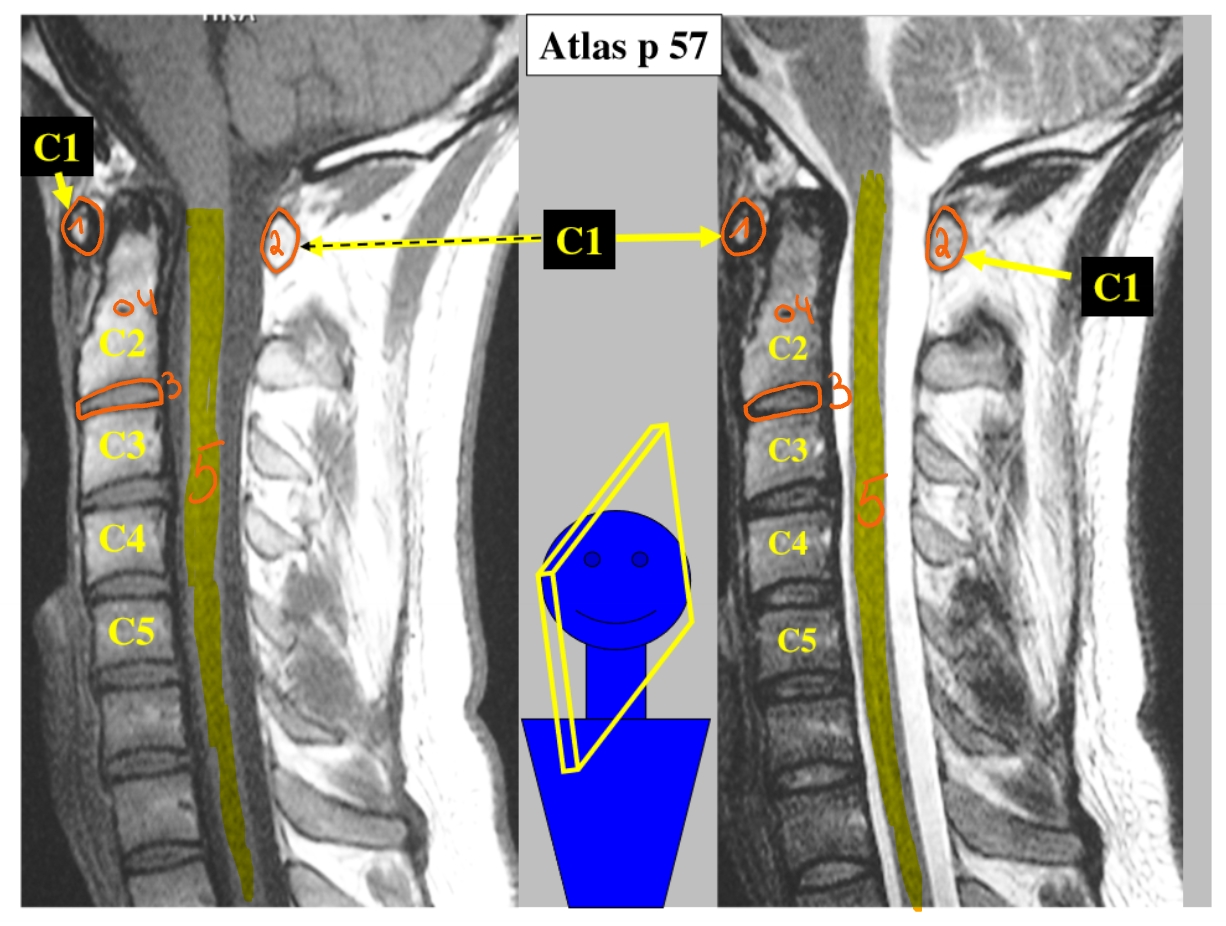

arcus anterior

arcus posterior

dens axis

processus uncinatus

corpus C4

processus uncinatus

processus spinosus C6

processus spinosus C7

corpus T1

processus transversus T1

→ T1: beste referentie => heeft grote processi transversi

arcus anterior C1

→ articulatio atlanto-axialisch-mediana = gewricht (daarrond roteren we ons hoofd)

dens axis

arcus posterior C1

processus spinosus C2

corpus C4

corpus C6

processus spinosus C7

processus articularis superior C6 & processus articularis inferior C6 → facetgewricht

processus spinosus C6

pedikel

= klein beenbrugje